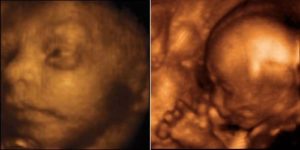

3Д УЗИ делается при беременности с целью детального просмотра частей тела, черт лица плода. При исследовании на экран ультразвукового устройства передается объемное голографическое изображение.

Трехмерное сканирование плода при беременности дает возможность в объемном виде оценить состояние ребенка. Картинка передается на экран аппарата в цветном режиме. Чаще метод используют на втором плановом скрининге, когда четко видны части тела плода.

Разница между 2Д- и 3Д-режимом состоит в том, что снимок после первой процедуры понятен для расшифровки только сонологу. Будущие родители не всегда понимают, где и что расположено у малыша на фото 2Д.

Трехмерное изображение представляется в 3 измерениях — глубине, высоте и ширине. Беременная может увидеть ребенка на экране УЗИ-аппарата в цвете. При этом детально просматривается каждая часть лица и тела, мимика плода.

У него неплохо выражены черты лица. Проводимое 3D-УЗИ в 25 недель позволит увидеть то, как будет выглядеть маленький человек, когда родится. Глаза еще закрыты, брови только начали развиваться, рот сформировался. Продолжает развиваться ушная раковина.